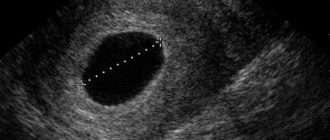

Причины неразвивающейся беременности пятница, мая 20, 2016 — 13:55 Плодным яйцом называется структура, окружающая